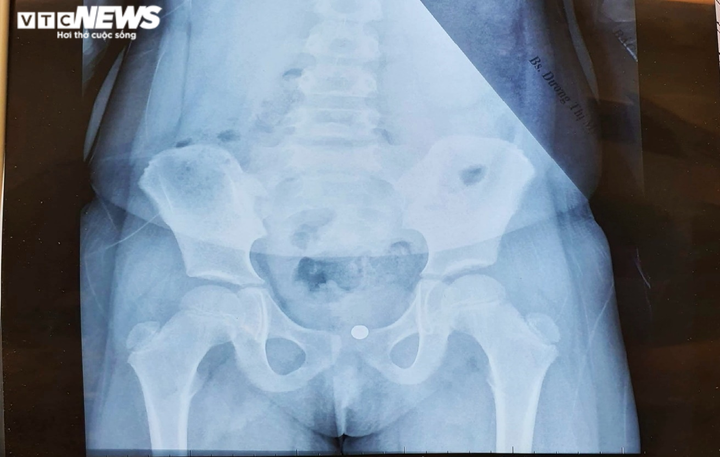

Các bác sĩ đã chụp chiếu các phim xác định vị trí của viên bi và mổ nội soi gây mê gắp dị vật trong âm đạo cho bé gái. Hiện sức khỏe và tâm lý bé T. đã ổn định.

Hình ảnh viên bi trong vùng kín từ phim chụp. (Ảnh:BVCC)